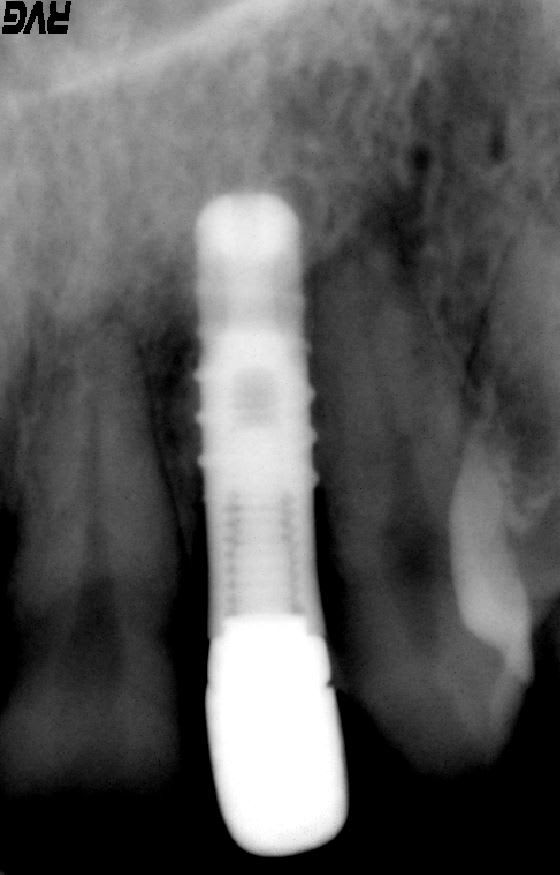

moi, je dirais un biotech

http://osseosource.com/dental-implants/product_info.php?manufacturers_id=144&products_id=1055

Double filetage intérieur?